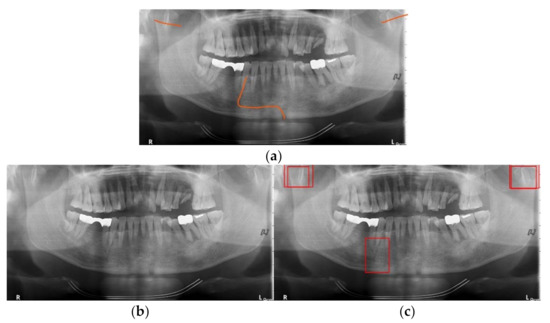

Mandibular fracture is one of the most frequent injuries in oral and maxillo-facial surgery. Radiologists diagnose mandibular fractures using panoramic radiography and cone-beam computed tomography (CBCT). Panoramic radiography is a conventional imaging modality, which is less complicated than CBCT. This paper proposes the [...] Read more.

Mandibular fracture is one of the most frequent injuries in oral and maxillo-facial surgery. Radiologists diagnose mandibular fractures using panoramic radiography and cone-beam computed tomography (CBCT). Panoramic radiography is a conventional imaging modality, which is less complicated than CBCT. This paper proposes the diagnosis method of mandibular fractures in a panoramic radiograph based on a deep learning system without the intervention of radiologists. The deep learning system used has a one-stage detection called you only look once (YOLO). To improve detection accuracy, panoramic radiographs as input images are augmented using gamma modulation, multi-bounding boxes, single-scale luminance adaptation transform, and multi-scale luminance adaptation transform methods. Our results showed better detection performance than the conventional method using YOLO-based deep learning. Hence, it will be helpful for radiologists to double-check the diagnosis of mandibular fractures. Full article

Show Figures